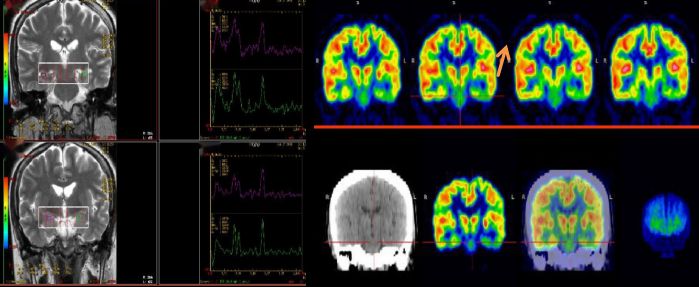

25歲,男,癲癇反復發作 MRS:雙側海馬區NAA降低,提示:神經元缺失;PET顯像提示:左側顳葉代謝減低,手術切除,術后病理提示符合局部腦組織缺氧病理改變,術后患者明顯好轉。